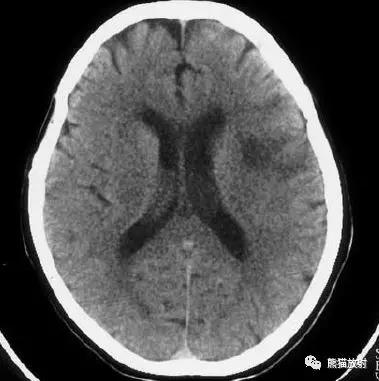

右侧豆状核梗死灶(发病后15d),明显均匀强化。另左侧丘脑见腔隙性梗死灶。

左侧大脑中动脉区域大面积梗死,明显不均质强化。

右侧大脑中动脉区域脑梗死,脑回样强化。

左侧额叶脑梗死(发病后12d),由于模糊效应平扫显示不清,增强扫描脑回样强化。

右侧基底节区脑梗死,增强后病灶看上去有所缩小。

出血性脑梗死

上矢状窦血栓形成,呈高密度(箭头);并邻近脑实质内出血性脑梗死。